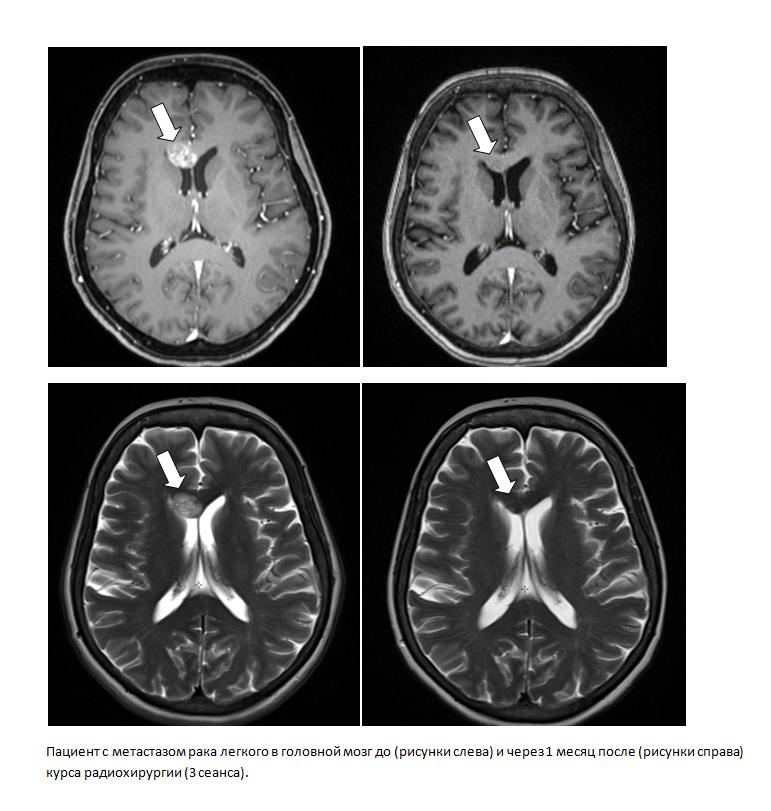

Применение новых технологий радиотерапии позволило снизить токсичность проводимого лучевого или химиолучевого лечения и практически полностью отказаться от вынужденных перерывов в лечении. Методика радиохирургии (облучение опухолевых очагов в ультравысокой дозе за 1–5 сеансов) внедрена в онкодиспансере в июле 2021 года. Всего в прошлом году радиохирургией пролечено 10 пациентов. Радиохирургический метод позволяет бескровно добиться радикального излечения опухоли при наличии у пациента медицинских противопоказаний к обширному хирургическому вмешательству (например, при раннем раке легкого), полностью заменяет хирургический метод при некоторых высокочувствительных к ионизирующему излучению опухолях (ранние раки предстательной железы), позволяет добиться хорошего клинического эффекта при метастатическом заболевании (метастазы в кости, головной мозг и в другие органы). В 2021 году радиохирургические курсы лечения выполнены двум неоперабельным пациентам с ранним раком легкого (с применением системы контроля дыхания), двум пациентам с ранним раком предстательной железы, одному пациенту с метастазом в печень, пяти пациентам с метастазами в головной мозг.